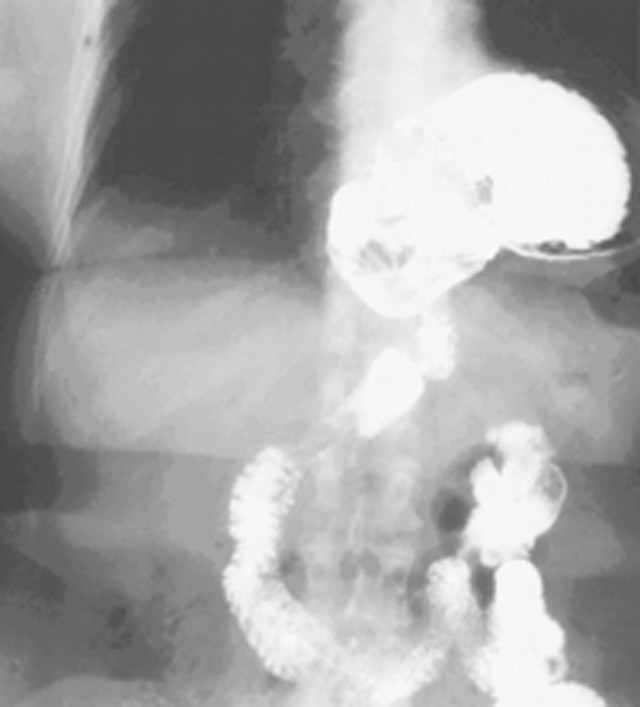

| Figure 1. Barium swallow |

Gastroesophageal reflux disease is extremely common in North America. The majority of these patients will have a simple type I hiatus hernia. The approach to this repair is usually by laparoscopic Nissen fundoplication. Much less frequently patients will present with a giant paraesophageal hernia (GPEH) (Figure 1). This type of hernia likely results from progression of a simple type I hernia with rolling of the fundus up alongside the gastroesophageal junction. Most patients are symptomatic, with dysphagia and heartburn being extremely common problems (Table 1). Rarely are patients truly asymptomatic. There are no absolute contraindications to the use of the laparoscopic approach.